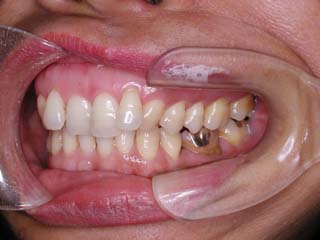

主訴:上の歯が出ている

診断名:顎関節症、上顎前突、叢生を伴う開咬

年齢:20歳

使用した主な装置名:TPB、マルチブラケット装置

抜歯/非抜歯および抜歯部位:抜歯(上顎左右第一小臼歯、下顎左右第二小臼歯)

治療期間:動的処置2年3か月、経過観察3年

費用の目安:保険適応 自己負担金として30~50万

リスク、副作用:外科手術によるリスク、マルチブラケット治療に伴う歯根吸収など偶発症が発生するリスクがある。

比較的強い叢生と、下顎の劣成長を伴う開咬が見られます。成長を終了した永久歯列ですので、骨の大きさのズレへのアプローチは大きく別れる所です。程度が小さければ、歯の傾きで補うように解決しますし、大きなズレであれば、外科的に骨のズレを改善する治療が選択されます。垂直的な問題はその他の不正咬合と比較して、解決が極めて困難な事が多いです。治療後の後戻りが頻繁に見られる不正咬合ですので、外科矯正での改善が望ましい場合も多いでしょう。

術前矯正の仕上げにスプリント治療を行った方が良い場合が多いです。現在、当院での治療では、術前に3か月のスプリント治療を必須にしております。せっかく手術までしてかみ合わせの位置を合わせようとしているのに、顎の関節の位置がずれていたらどうなるでしょう。顎の関節は往々にして顎の大きさのズレをカムフラージュするような偏位を示すので、術後にじわじわと後戻りしているような現れ方で、ズレが見えてくるのでは?このスプリント治療を徹底できたケースでは術後の安定性が極めて高いと感じています。

外科手術は、上顎のインパクションのみをLeFort1にて行いました。